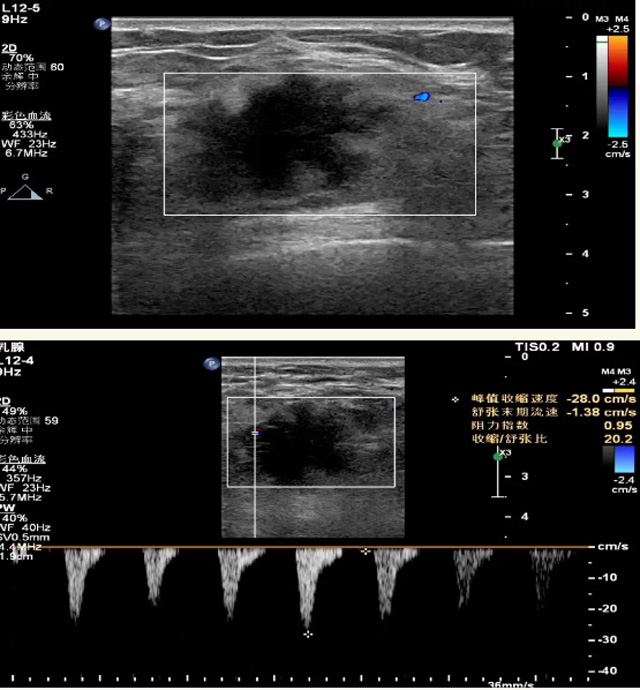

乳腺B超檢查無輻射,對囊性病變敏感,可以實(shí)時(shí)觀察病灶。超聲引導(dǎo)活檢跟手術(shù)前的定位。就是它對于微小的鈣化查出率比鉬靶稍微差點(diǎn)。磁共振MRI檢查也是是沒有輻射的,對備孕跟已經(jīng)懷孕的人士比較友好。不用擔(dān)心這個(gè)輻射影響胎兒問題。對乳腺病灶敏感性較高,致密乳腺病灶、乳腺癌的復(fù)發(fā),準(zhǔn)確鑒別囊性及實(shí)性病變??梢詭椭R床醫(yī)生判斷惡性、良性病變。但是MRI磁共振對微小鈣化不明顯,微鈣化還是鉬靶靠譜點(diǎn)。檢查時(shí)間比較長,有偽影的影響。費(fèi)用相對B超,鉬靶高很多。